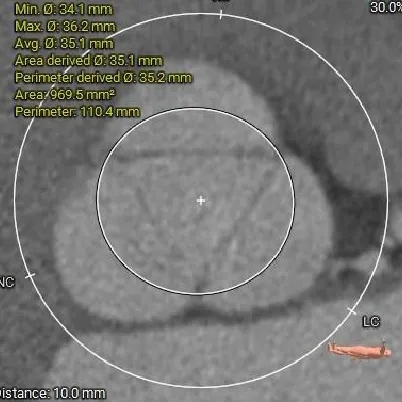

瓣上结构测量

瓣上8mm

33.7mm

瓣上10mm

35.2mm

瓣上空间逐渐增大,仅瓣上2mm左右可提供锚定